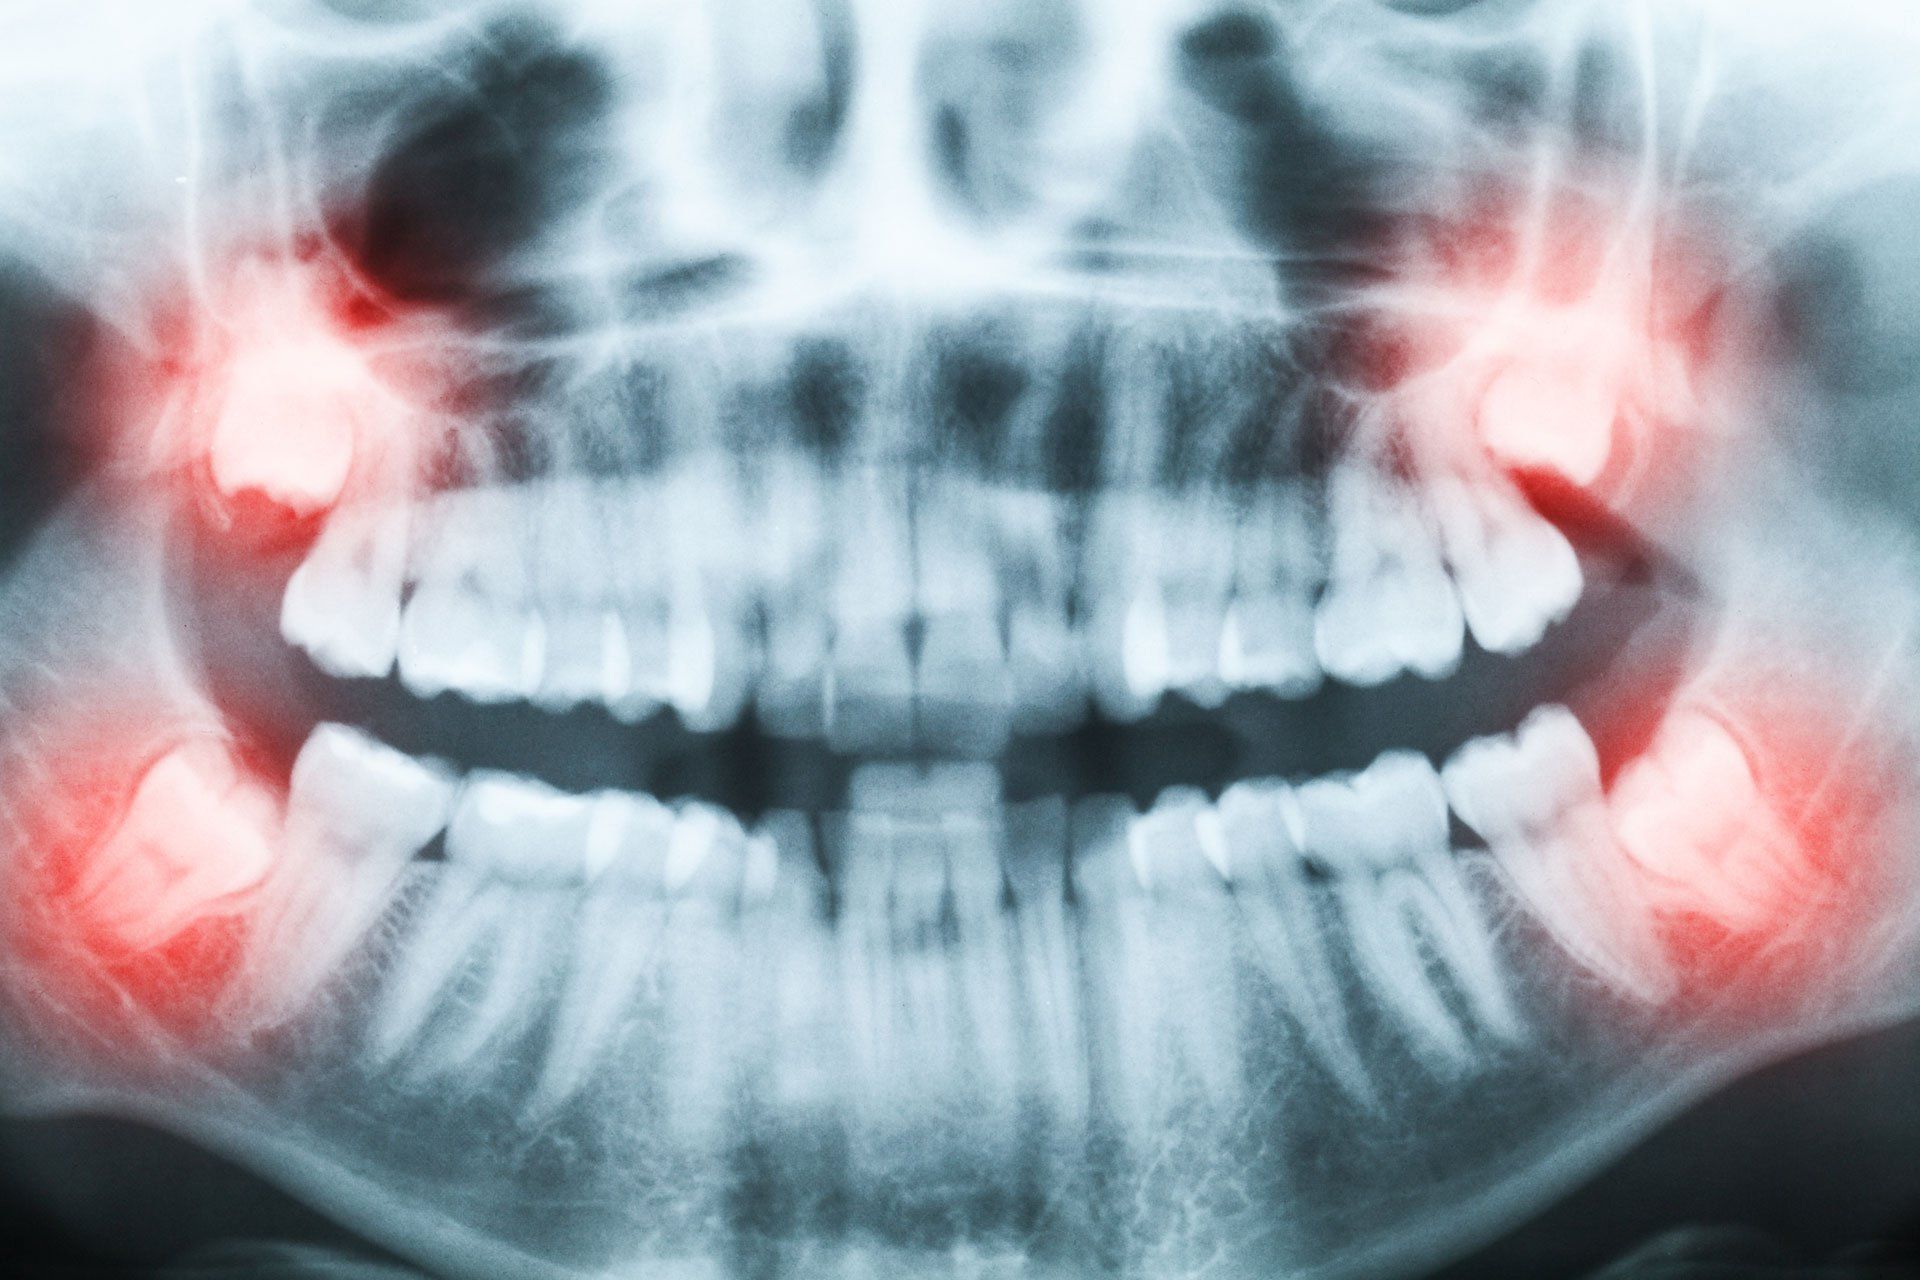

Our oral surgery services consist mainly of tooth and wisdom tooth extractions, but we perform other surgery procedures as well. Ask us today if you have jaw pain or questions about the types of oral surgery we perform.